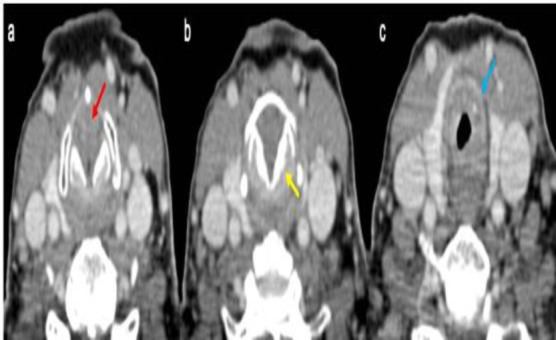

Case report: We report the case of a woman in her 70s, who was previously tracheostomized at another facility and was presented to our attention with glottic-subglottic stenosis. We performed a lysis of glottic synechia and subglottic debulking via transoral laser microsurgery, yielding satisfactory results over the short term. However, a relapse occurred within two months, along with ulcerative lesions on the nasal septum. Biopsies revealed multinucleated giant cells and inflammation suggestive of vasculitis. Based on the histological and clinical features, a diagnosis of vasculitis was considered. Anti-Neutrophil Cytoplasmic Antibodies testing was positive. A rheumatological examination confirmed the hypothesis of Granulomatosis with Polyangiitis. The lack of typical symptoms was the main reason for the delayed diagnosis.